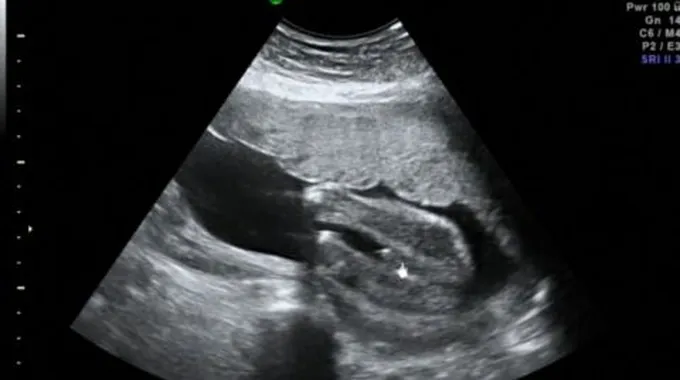

عادة ما يُستخدم فحص السونار أو التصوير بالموجات الصوتيّة (بالإنجليزيّة: Fetal Ultrasound) خلال فترة الحمل بهدف تصوير الجنين داخل الرحم (بالإنجليزيّة: Uterus)؛ حيثُ يتم من خلاله تقييم قلب الجنين، ورأسه، وعموده الفقري، وغيرها من أعضاء جسم الجنين، ويعتمد جهاز السونار في عمله على الموجات الصوتيّة المُطلقة عن طريق جهاز إلكتروني يُدعى بمُحوّل الطاقة (بالإنجليزيّة: Transducer)، ومن خلال انتقال الموجات الصوتيّة عبر طبقات الجلد، والعضلات، والسوائل، والعظام، ومن ثمّ انعكاسها؛ تنتج صورة إلكترونيّة للجنين على الجهاز، ويتم تطبيق مادة هُلاميّة على البطن عند إجراء الفحص بهدف تعزيز انتقال الموجات الصوتيّة وتسهيل حركة الجهاز على سطح البطن، وتجدر الإشارة إلى أنّ فحص السونار يُعدّ من الفحوصات الآمنة لتقييم الحمل؛ وذلك لعدم استخدام أي موجات إشعاعيّة خلال إجراء الفحص سواء كان عبر التصوير بالموجات الصوتيّة عن طريق المهبل (بالإنجليزيّة: Transvaginal Ultrasound)، أو التصوير بالموجات الصوتيّة عبر البطن (بالإنجليزيّة: Transabdominal Ultrasound).[1][2]

في الحقيقة، هنالك ثلاثة أنواع مختلفة من فحص السونار أو الفحص بالموجات الصوتيّة: الفحص الاعتيادي أو الفحص ثنائي الأبعاد، وفحص دوبلر (بالإنجليزيّة: Doppler Ultrasound) الذي يقوم بقياس حركة الدم خلال الرحم وجسم الجنين، بالإضافة للفحص ثلاثيّ الأبعاد (بالإنجليزية: 3D Ultrasound) الذي يقوم بتزويد صورة مُطابقة للجنين،[1] وتجدر الإشارة إلى أنّ الفحص ثلاثيّ الأبعاد هو أكثر هذه الفحوصات دقة في تحديد جنس الجنين، وعادة ما يتم فحص السونار لتحديد جنس الجنين بعد الأسبوع الـ18 من الحمل؛ حيثُ إنّه قبل ذلك يكون البظر (بالإنجليزيّة: Clitoris) في جنين الأنثى يُساوي حجم العضو الذكري في الجنين الذكر، ممّا يؤدي إلى صعوبة التفريق بينهما، وتعتمد دقة النتيجة بشكل عام على العديد من العوامل: كعمر الجنين، ونوع الجهاز المُستخدم، والطبيب الذي يُجري الاختبار، بالإضافة لوضعيّة الجنين عند إجراء الفحص، ولذلك فمن الممكن ألّا تكون النتيجة صحيحة في العديد من الأحيان، وتكون الطريقة الوحيدة لتأكيد جنس الجنين بشكل كامل هي الانتظار حتّى الولادة، وفيما يلي بيان لبعض من العلامات والإشارات التي قد تظهر خلال فحص السونار ويتم من خلالها محاولة تقييم جنس الجنين:[3][4][5]